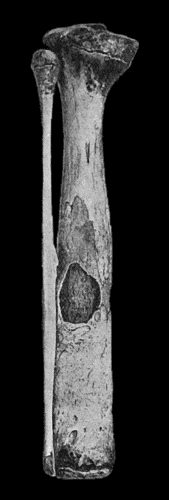

120.Segment of Tibia resected for Brodie's Abscess 449

121.Radiogram of Brodie's Abscess in Lower End of Tibia 451